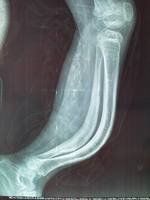

如何判断骨折?

疼痛、肿胀、活动受限

骨折特有体征

1、畸形:骨折端移位使患肢外形发生改变,主要表现为缩短、成角、延长。

2、异常活动:不能活动的部位出现活动。

3、骨擦音或骨擦感:骨折后两骨折端相互摩擦撞击。